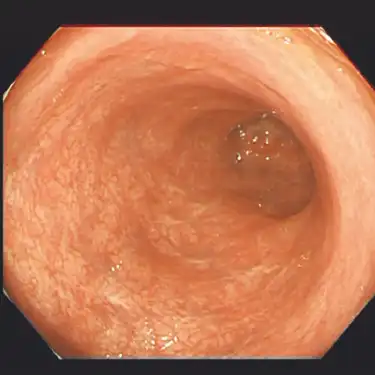

治療前 -

最近では症状がほとんどなく、検便検査を契機に病気が見つかる人も増えています。潰瘍性大腸炎の原因は解明されておらず、何か一つの原因があるのではなく複数の要因が絡み合って発症するものと考えられています。専門の先生には誤解を招く表現になるのですが、腸に起きたリウマチやアトピーのような病気と考えていただくとわかりやすいかもしれません(実際にリウマチとは多くの治療方法が共通しています)。

治療後(半年後) -

大腸粘膜の炎症を抑え、症状をコントロールすることで日常生活を病気発症前と同じレベルで行えるようにすること(臨床的寛解)が第一の目標となります。また症状がなくても内視鏡で炎症が残存していると再燃のリスクと大腸がんの発症リスクが増加することが知られており、定期的な内視鏡検査と治療の継続が非常に重要になります。